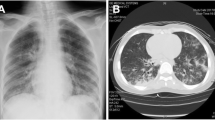

Mutation of the sic promoter or the rocA gene is important in STSS pathogenesis of mice

In the 10 STSS emm1 isolates, we found mutations in the sic promoter, the csrR promoter, or the rocA gene that conferred increased virulence gene expression. It is well-established that virulence is enhanced upon inhibition of csrS/csrR gene expression6. To elucidate the role of the sic promoter or rocA in STSS infection in vivo, we injected Se235 isolates with either the rocA or sic promoter mutation or Se235 alone in GAS model mice and compared the lethality between the two groups. The mutant strains showed significantly higher lethality than the Se235 strain (p < 0.05) (Fig. 4). This result suggested that sic promoter-mutated and rocA-mutated emm1 strains isolated from STSS patients are more virulent than strains isolated from patients with non-invasive infections.

Mutation of rocA gene and sic promoter enhances the lethality of GAS mouse model.

Survival curves of mice infected with either rocA (Se235rocA) or sic promoter (Se235sicP*) mutant strains or non-STSS Se235 strain. Mice were intraperitoneally inoculated with 4 × 107 CFU of each GAS strain and survival was observed for eight days post-infection. Mortality differences were statistically significant (p < 0.05) between Se235 and Se235sicP* and between Se235 and Se235rocA, as determined by a log-rank test. Survival curves were generated from three independent experiments using a total of 12 ddY mice for each strain.